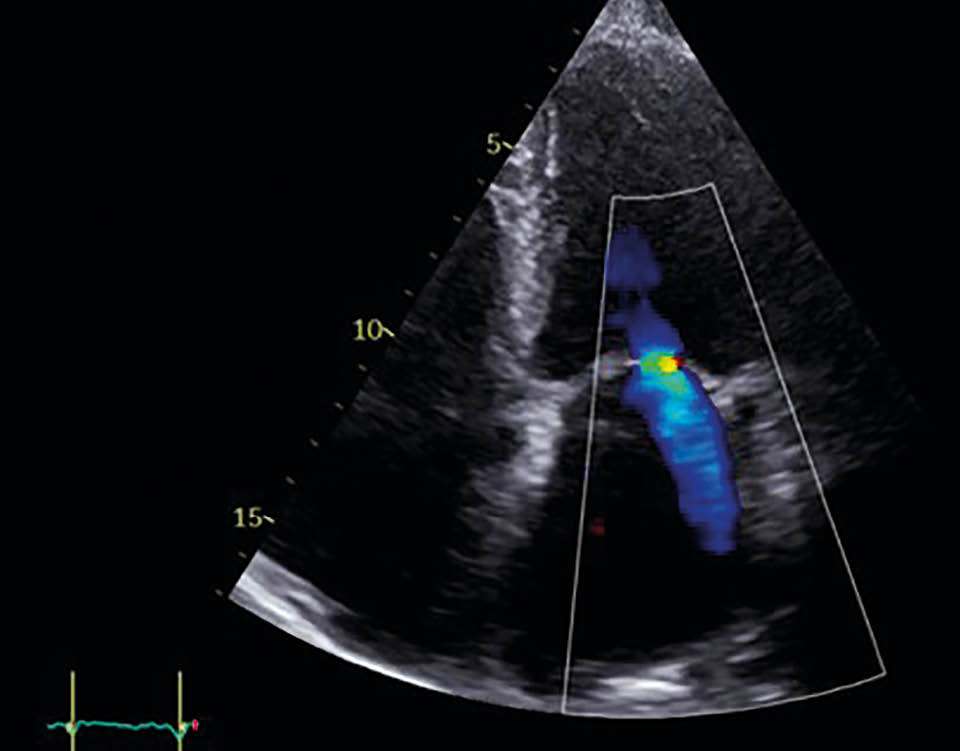

Mitralklappeninsuffizienz in TTE nach der Behandlung

Abbildung 3d: Mitralklappeninsuffizienz in TTE

nach der Behandlung

Postinterventionell zeigte sich echokardiografisch eine Reduktion der MI auf Grad 1 mit deutlicher Abnahme des EROA auf 0,1 cm2. Die Patientin berichtete bereits am ersten postinterventionellen Tag über eine deutliche Besserung der Dyspnoe. Die Entlassung erfolgte am zweiten postprozeduralen Tag unter stabilen hämodynamischen Verhältnissen. Die strukturelle Nachsorge ist über den niedergelassenen Kardiologen in enger Zusammenarbeit mit der kardiologischen Klinik organisiert (TTE-Kontrollen nach 1, 3 und 6 Monaten, Laborparameter, 6-Minuten-Gehtest [6MWT]).